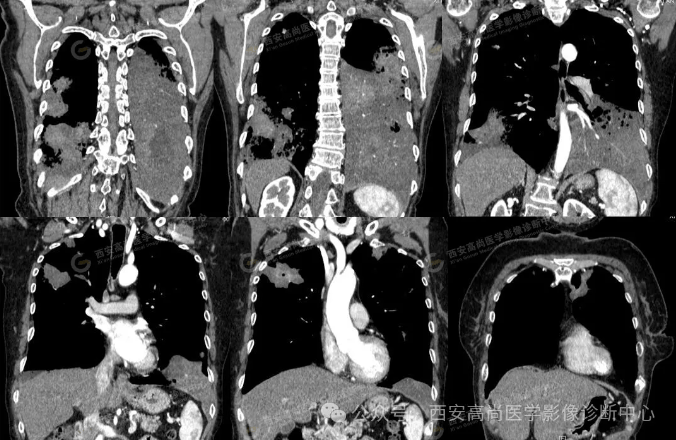

pet/ct病例—肺粘液腺癌,历经3年余终确诊【西安高尚医学影像诊断中心